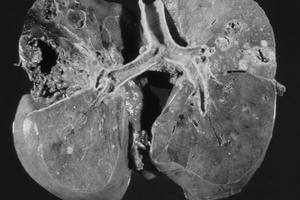

Туберкулез почки

Гематогенное распространение туберкулезных бацилл в почки из первичного инфекционного очага, которым обычно являются легкие, приводит к образованию туберкулем в капиллярах клубочка. Затем бациллы распространяются вдоль нефрона к петле Генле. Впоследствии происходит формирование гранулемы, которое сопровождается казеозным некрозом почечного сосочка и деформацией полостной системы.

Примерно у половины пациентов на обзорной урограмме определяются кальцифи-каты в почках. Несмотря на то, что почечный туберкулез — это двухстороннее поражение, обычно одна почка поражена сильнее. Выделение контрастного препарата слабее на более пораженной стороне. Паренхима почки деформирована и может быть полностью разрушена (аутонефрэктомия). Мелкие чашечки расширены и имеют неправильное строение, может выявляться внутрипочечный свищ. Мочеточники могут быть распрямлены или сужены, объем мочевого пузыря — снижен. Для почечного ТБ патогномоничным является наличие инфундибулярного стеноза. У детей и тех пациентов, которым была проведена ранняя диагностика, ВВУ может быть нормальной.

Отсутствие функции почки на ВВУ при нормальных показателях ультразвукового исследования должно заставить врача, по крайней мере, заподозрить ранние проявления ТБ почек, так как при таких данных у пациента могут быть диффузные паренхиматозные туберкулемы. На более поздних этапах, с развитием глубокой ка-ликоэктазии и при сокращении почечной лоханки, определяется так называемый "малярийный признак" — кольцо из расширенных чашечек, часто представленное без отображения почечной лоханки.